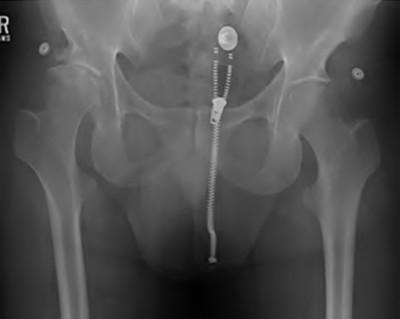

An 82-year-old woman falls and sustains the fracture shown in figure A. She denies any history of dislocation or prodromal pain prior to her fall. What is the most appropriate treatment?

The radiograph demonstrates a periprosthetic femur fracture extending to the tip of the stem. The long spiral fracture is consistent with a loose implant. The bone stock is sufficient. Therefore, this fracture pattern would classify as a B2 using the Vancouver classification system. The Vancouver classification for periprosthetic femoral fractures is simple yet incorporates all the pertinent factors such a location, stem fixation, and bone stock. Type A is a trochanteric fracture- lesser or greater. These can be treated non-operatively usually and ORIF if symptomatic. Type B fractures are around or just below the stem and are subdivided into three types. Type B1 is a fracture with a well fixed stem.

The treatment is cable plating or allograft struts or a combination of the two. Type B2 is a fracture with a loose stem with good bone stock. The treatment is a cementless porous coated long stem atleast two diameter length past the

fracture site. Type B3 is a fracture with a loose stem and comminution. For younger patients, use cementless porous coated long stems with allograft struts. For older patients, consider a tumor prosthesis. Cement fixation is sometimes necessary Type C is a fracture well below the stem tip. These can be treated independently of the prosthesis.

Springer et al showed optimal outcomes with revision involving long extensively-coated femoral stems for Vancouver B fractures.

Masri et al review the classification and treatment of periprosthetic femur fractures.

A 72-year-old male presents 2 years status post fixation of an impending pathologic right femur fracture due to metastatic renal cell carcinoma. He is minimally ambulatory due to pain. Despite radiation therapy, there has been progression of the lesion with extensive cortical bone loss, which is shown in Figure A. A proximal femoral replacement arthroplasty is performed without complications, and is demonstrated in Figure B. Which of the following is true regarding this patients post-operative course?

Deep prosthetic infection is the most common complication after hip arthroplasty performed for salvage of failed internal fixation after pathologic proximal femoral fracture secondary to malignancy.

Jacofsky et al reviewed the complications in 42 patients with a mean age of 63 who were treated with hip arthroplasty for salvage of failed treatment of a pathologic proximal femoral fracture. Multiple different constructs were used.

The most common complication was deep prosthetic infection, which occurred in nearly 10% of the patients studied. All infections occured in patients whom had previously received radiation. The mean Harris Hip score improved from 42 to 83 points post-operatively, and 41 of the 42 patients were ambulatory at follow-up. Implant survivorship free of revision for any reason at 5 years was 90%, and free of revision for aseptic failure or radiographic failure was 97%.

Figure A shows a lytic lesion of the proximal femur with an intramedullary implant. Figure B shows a proximal femoral replacement.